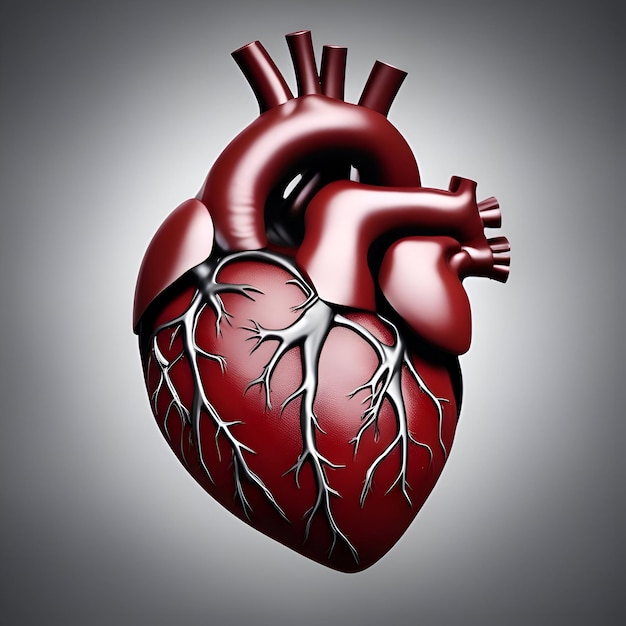

Анатомия желудка и сердца: визуализация и изучение

Раздел: Фотопанорама